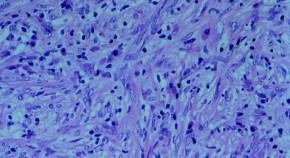

Alex Kentsis and colleagues identify somatic genomic rearrangements in primary human rhabdoid tumors characterized by deletions and inversions involving PGBD5-specific signal sequences at their breakpoints. They further show that ectopic expression of PGBD5 in primary immortalized human cells is sufficient to promote cell transformation in vitro and in immunodeficient mice in vivo, thus defining PGBD5 as an oncogenic mutator and providing a plausible mechanism for site-specific DNA rearrangements in solid tumors.